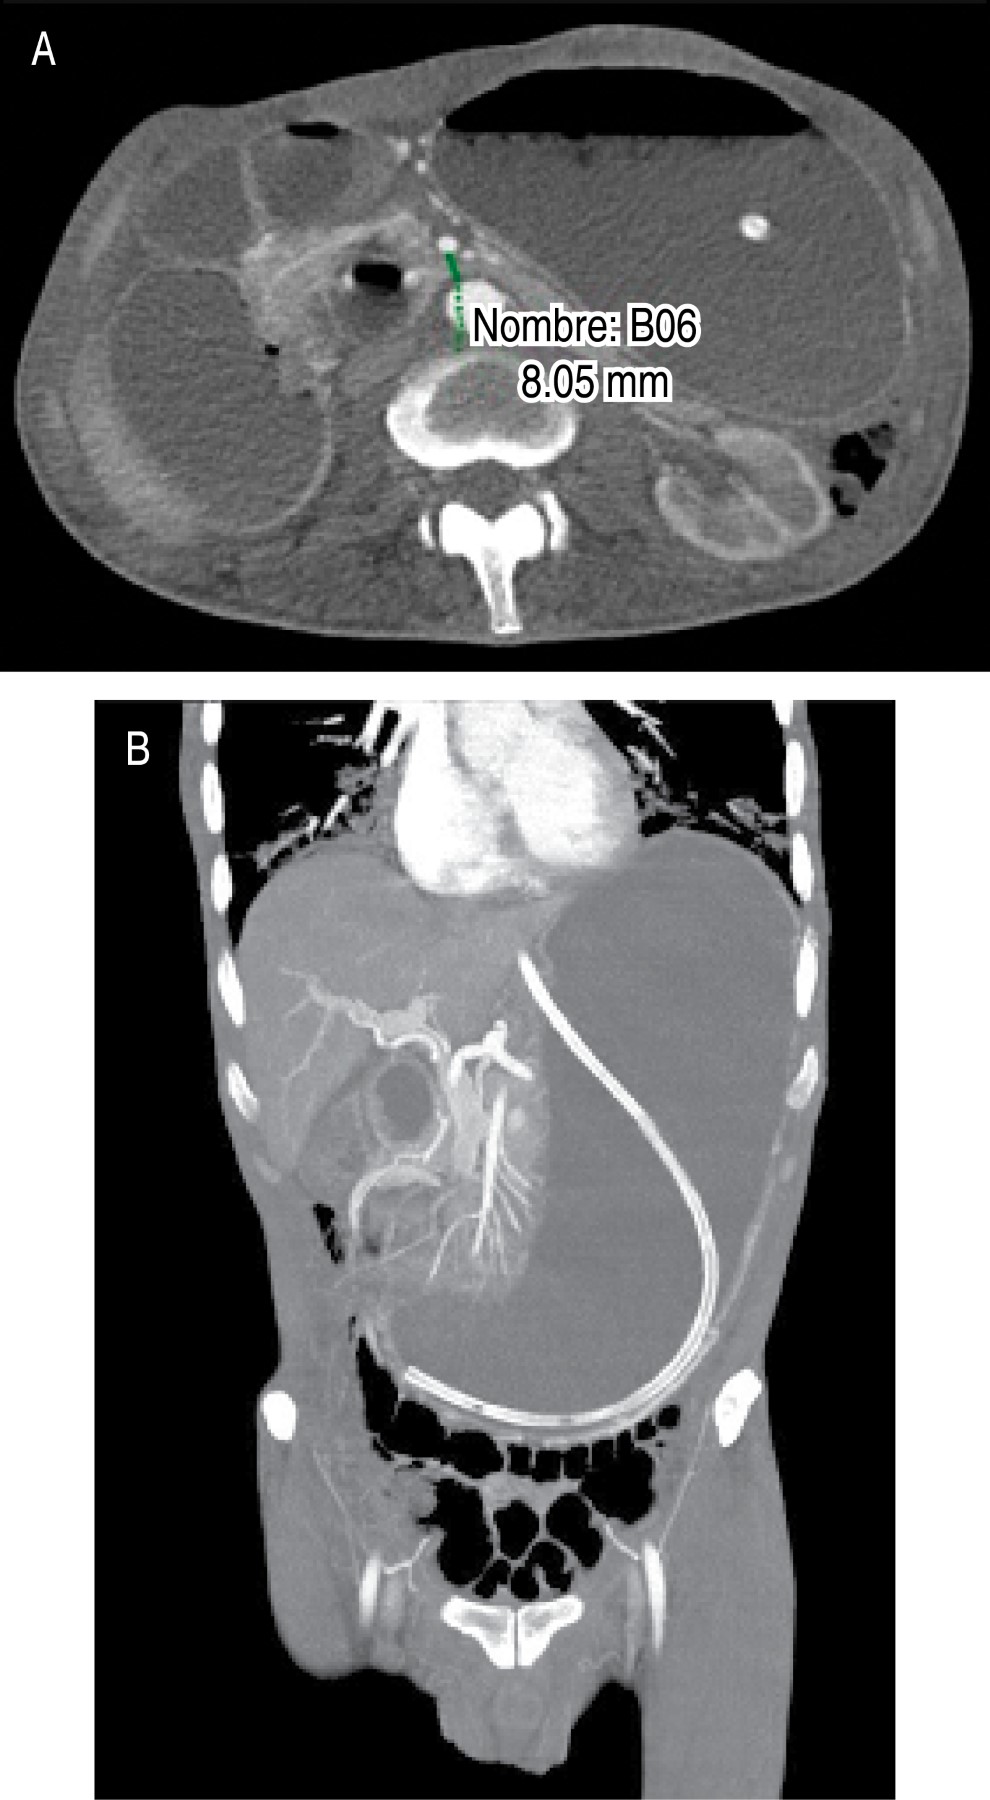

Diagnostic studies require a high index of suspicion since symptoms may be nonspecific. Diagnostic imaging criteria include: 1) Duodenal obstruction with an abrupt cut in the third portion. 2) Aortomesenteric angle less than 25o (considered the most sensitive measure of the diagnosis). 3) Aortomesenteric distance less than 8 mm. 4) High fixation of the duodenum by the ligament of Treitz.8

An abdominal CT scan was performed in which gastric dilatation was identified with loss of gastric folds and decreased distance between the aorta and superior mesenteric artery, measuring 8.05 mm (Figure 1). The sagittal section of the CT scan showed an acute aortomesenteric angle of 14.92o (Figure 2). Since his admission, he received management with gastric decompression through a nasogastric tube, water and electrolyte replacement, analgesics, and antibiotic therapy with a third-generation cephalosporin antibiotic; however, the obstruction persisted despite conservative management for 48 hours, so surgical management was proposed and accepted. A laparoscopic approach with five ports was performed; the transverse colon was mobilized, and the site of obstruction was seen as secondary to clamping of the superior mesenteric artery between the third and fourth portion of the duodenum. A mechanical duodenojejunal-anastomosis was performed at 60 cm from the ligament of Treitz; the gastroenterostomy was closed in two planes with slow absorption monofilament suture for the first plane and non-absorbable for the second one. Postoperative evolution was good. He started drinking liquids at 24 hours and progressed to a soft diet at 48 hours. He was discharged home due to improvement 48 hours after the procedure. There have not been any subsequent clinical sequelae after two months. He has had adequate tolerance to the oral route, but the patient has not attended to control for post-surgical follow-up.

Figure 1